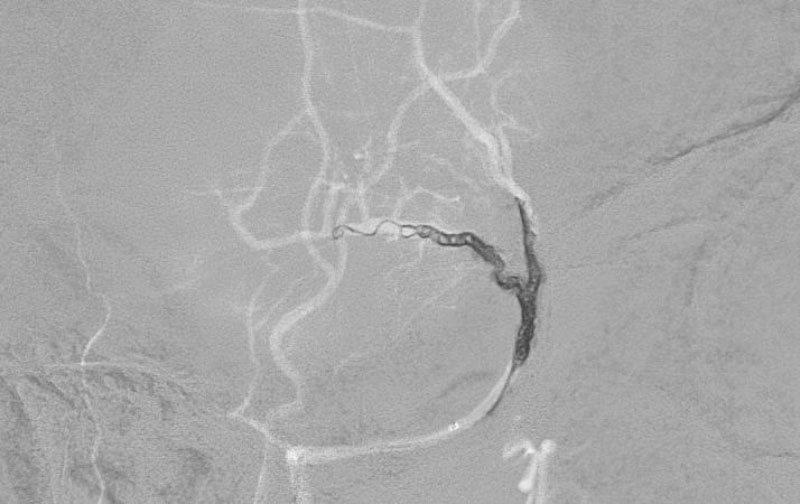

症例 '25年11月

No.

1598

'25年11月26日

右円蓋部髄膜腫

40代

大阪府の病院

手術写真

治療

前

中

後